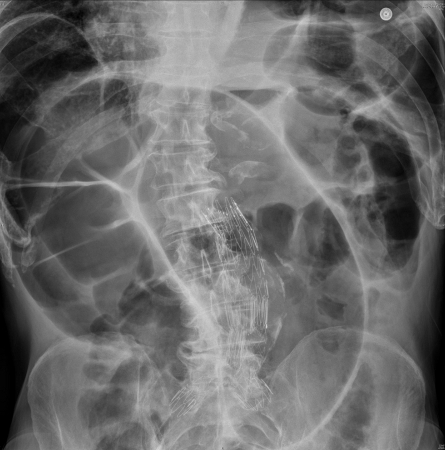

An x-ray may show the colon distended to the point of the obstruction with a paucity of distal gas or signs more classically associated with colonic volvulus. Approximately 75% of colonic volvulus can be diagnosed on x-ray.[31]Mutch MG, Birnbaum EH, Menias CO. Diagnostic evaluations-radiology, nuclear scans, PET, CT colography. In: Wolff BG, Fleshman JW, Beck DE, et al, eds. The ASCRS textbook of colon and rectal surgery, 1st ed. New York, NY: Springer; 2007:57-100.[32]Jaffe T, Thompson WM. Large-bowel obstruction in the adult: classic radiographic and CT findings, etiology, and mimics. Radiology. 2015 Jun;275(3):651-63.

Sigmoid volvulus shows a dilated inverted U-shaped loop of colon (resembling a coffee bean or bent inner tube) projecting toward the right side of the abdomen.[8]Tian BWCA, Vigutto G, Tan E, et al. WSES consensus guidelines on sigmoid volvulus management. World J Emerg Surg. 2023 May 15;18(1):34.

Opposing colonic walls produce a radio-opaque line. Proximal large and small bowel dilation may also be evident. In cecal volvulus, dilated right colon rotates to the left side and dilated small bowel may also be present.

[Figure caption and citation for the preceding image starts]: Large bowel obstruction. Plain radiograph showing distended large bowel loops. Note grossly dilated caecum (white arrow)Musson RE, Bickle I, Vijay RKP, et al. Gas patterns on plain abdominal radiographs: a pictorial review. Postgrad Med J. 2011 Apr;87(1026):274-87; used with permission [Citation ends].